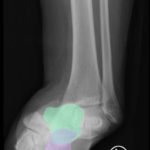

The X-rays were significant for a subtalar dislocation. The calcaneus (red) is laterally displaced with respect to the talar head (orange), and the white lines indicate the normal articular surface. Additionally, there was a talonavicular dislocation, as seen in the fourth image: the talus (green) and navicular bone (purple) overlapping suggests a dislocation. In a normally aligned foot, the boundaries of the two bones create a point of articulation.